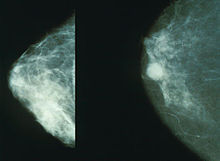

美國《CBS》報導表示,許多人感覺乳房有腫塊時,就認為可能是罹患乳癌,但是這觀念是錯誤的。雖然這是典型的跡象,但「女性需要了解其他症狀,包括乳房形狀改變、皮膚凹陷、乳頭分泌物或是皮膚出現紅色鱗屑狀斑塊等。」紐約撒隆凱特林癌症紀念中心的克利福德‧胡蒂斯博士表示,「雖然婦女會定期做乳房攝影術,但美國癌症協會建議,40歲以上女性應每年開始定期做檢查,追蹤自己身體上的變化。」

美國德克薩斯大學乳腺癌研究在納歐頭‧上野博士向《CBS》表示,「有乳癌家族史的女性比其他人罹乳癌風險更高。」英國醫療首席薩莉‧戴維斯教授也表示,「不是只有年老時才會得乳癌,婦女應留意乳房、乳頭形狀及皮膚周圍的任何變化。」胡蒂斯強調,雖然辨認乳癌潛在不同的跡象很重要,但為了保險起見,應看醫生比較妥當。